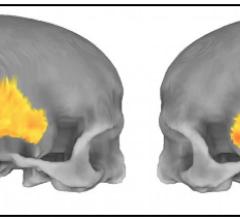

Researchers from the National Institute of Mental Health (NIMH) have produced the first direct evidence that parts of our brains implicated in mental disorders may be shaped by a “residual echo” from our ancient past. The more a person’s genome carries genetic vestiges of Neanderthals, the more certain parts of his or her brain and skull resemble those of humans’ evolutionary cousins that went extinct 40,000 years ago, said NIMH’s Karen Berman, M.D. NIMH is part of the National Institutes of Health.